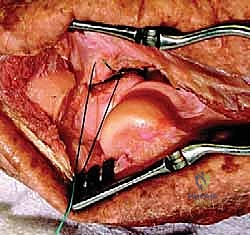

- في إصابات الثالوث الرهيب، يبدأ التمزق عادة من هذه الجهة (الخارجية) ويمتد نحو الداخل. يتضمن نمط الإصابة تمزقاً كاملاً في هذا الرباط من منشئه على اللقيمة الوحشية للعضد، تاركاً وراءه "بقعة عارية" (Bare Spot) مميزة على العظم يراها الجراح بوضوح أثناء العملية.

العلاج الجراحي (الرد المفتوح والتثبيت الداخلي - ORIF) - المعيار الذهبي

تهدف الجراحة مع الأستاذ الدكتور محمد هطيف إلى إعادة بناء الكوع من الداخل إلى الخارج ليكون مستقراً كفاية للسماح للمريض بتحريك ذراعه في اليوم التالي للجراحة مباشرة.

مبادئ الجراحة المتقدمة:

الجراحة ليست مجرد وضع مسامير؛ إنها عملية ترميم ميكانيكي دقيقة تعتمد على بروتوكول متسلسل عالمي:

1. تثبيت أو استبدال رأس الكعبرة.

2. تثبيت الناتئ الإكليلي.

3. إصلاح الرباط الجانبي الوحشي (LCL).

4. تقييم وإصلاح الرباط الجانبي الإنسي (MCL) إذا لزم الأمر.

الدليل الشامل خطوة بخطوة: كيف يجري الدكتور هطيف جراحة الثالوث الرهيب؟

تُعد هذه الجراحة من أصعب العمليات في طب العظام، وتتطلب مهارة استثنائية. إليك نظرة مفصلة لما يحدث داخل غرفة العمليات مع الأستاذ الدكتور محمد هطيف: